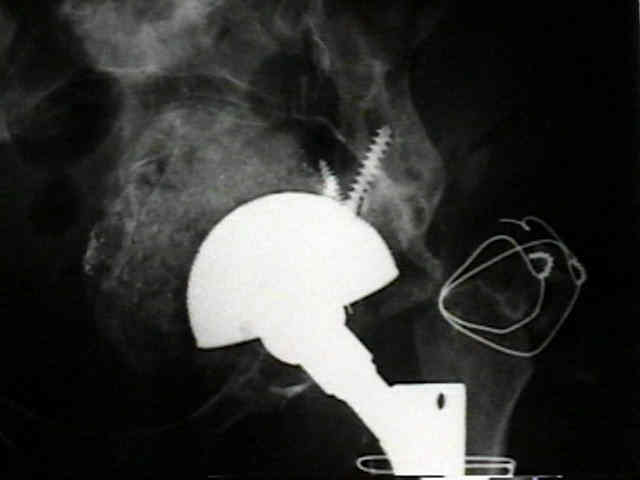

radiographic signs of ingrowth fixation

(from Moore MS, et al.)

- 97 percent of the cups with three or more of these signs were determined to be stable at the time of revision surgery

- in contrast, 83% of the cups with two or fewer signs were loose.

- five radiographic signs of stable cup fixation:

- absence of radiolucent lines

- presence of a superolateral buttress

- medial bone stress-shielding

- radial trabeculae

- inferomedial buttress

radiographic signs of loosening

- radiolucent lines that initially appeared after two years

- progression of radiolucent lines after two years

- radiolucent lines in all three zones

- radiolucent lines 2 mm or wider in any zone

- migration

- loosening is present w/ more than 2 mm of migration (either horizontal or vertical);

- continuous radiolucent line;

- note that peripheral radiolucent lines which are non-continuous are commonly found in press fit acetabular components and are often not progressive;